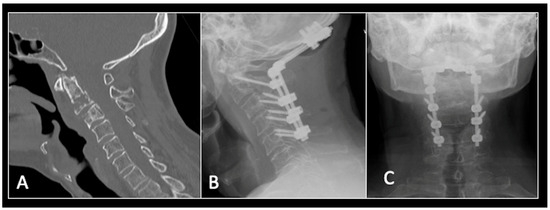

2.3. Case 3: Cervical Chordoma

This 68-year-old male was referred to our institution with a 4 cm cervical mass localised to C2/3 following investigations for left-ear congestion and altered hearing (Figure 7). A CT-guided biopsy confirmed a conventional chordoma. The patient underwent separation surgery with adjuvant proton beam therapy. There was no evidence of disease progression on 3-monthly surveillance imaging (Figure 8). Approximately 12 months following separation surgery, the patient presented with acute onset neck pain. A C2 odontoid peg fracture was diagnosed requiring a posterior occipitocervical stabilisation procedure (Figure 9). Pre-stabilisation MRI imaging confirmed no tumour progression (Figure 10).

Figure 7.

The MRI demonstrates a left-sided lobular mass (arrow) with invasion of the C2/3 vertebral body and epidural extension, but no cord compression. The yellow line on the axial image indicates the axial slice level. (A) T2W sagittal; (B) T1W sagittal; (C) T2W axial.

Figure 9.

(A) Sagittal CT imaging showing pathological fracture of C2 vertebral body. (B,C) Posterior occipitocervical stabilisation on lateral (B) and AP (C) radiographs, respectively.

Figure 10.

RI demonstrating no tumour (arrow) progression with wide circumferential margins around the spinal cord. The yellow line on the sagittal images represents the level of the axial plane. (A) T2W sagittal; (B) T1W sagittal; (C) T2W axial.